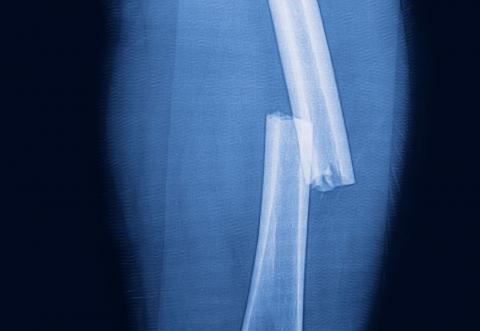

My femur had shattered while I was hiking in the rugged Rugova Mountains of western Kosovo. That this is part of a range called the Accursèd Mountains was painfully prophetic. I was walking, not slipping or sliding, when I felt a crack and a stab in my right thigh and I couldn’t stand up anymore. My face turned white from shock.

At the emergency entrance to the local hospital, the staff brought a wheelchair with no leg supports. Bending my swollen leg was out of the question, so Endrit held it up as Yari wheeled me around the hospital. From the ER we went to a dark room with an ancient-looking x-ray machine. A lab technician took only one x-ray, while Endrit and Yari waited beside me, and Endrit held my leg to keep it from bending. No lead aprons, no protective barriers.

Desperate situations call for desperate measures. With my iPad, I tracked down the emails of the CEOs for my insurance company at its headquarters in France, plus Italy and the US. I pleaded my dire straits—weakening by the hour, in need of an operation and possibly a transfusion immediately, and no one was getting me out of Kosovo. I included copies of the grainy x-ray and the sketchy blood test results.